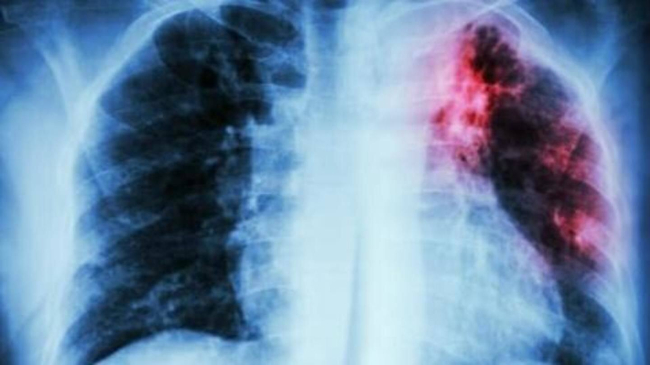

Соответственно, увеличилось число поздних тяжёлых форм туберкулёза, которые сопровождаются распадом лёгочной ткани, бактериовыделением. Пациенты обращаются к врачу уже по факту, по клиническим проявлениям. Оставаясь долгое время дома, не проходя флюорообследование, больные заражают детей, отсюда и небольшой рост детского туберкулёза.